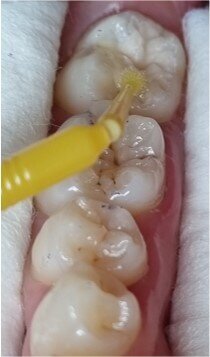

Once the copy of the occlusal face had been obtained, the lesion of tooth #47 was opened with a small round diamond bur at high speed and under abundant water irrigation. The resulting Class I cavity (Fig. 4) was restored with EQUIA Forte HT (Shade A2). Once the relative isolation with cotton rolls had been done, a very thin layer of GC Cocoa Butter (GC Europe) was applied to the adjacent teeth and areas where the glass hybrid was not to adhere. Owing to the good handling properties and the handy capsule format of EQUIA Forte HT, the material can be homogeneously mixed and injected into the cavity fast and easily. By applying the content of a single capsule, we managed to cover the cavity completely, and then we placed the stamp (Fig. 5), previously obtained with the low-viscosity resin, and pressed firmly on top of the tooth and restorative material. Excess was removed with the help of a spatula and probe during the rubbery phase of the glass hybrid. The stamp was removed, revealing the beautifully reproduced occlusal anatomy (Fig. 6). No separating agent, such as glycerine or PTFE tape, was required since the stamp does not stick to the glass hybrid material. When a resinous stamp is used, light-polymerising a resin composite restoration with the stamp in situ might cause issues—owing to light attenuation as well as co-polymerisation of the stamp with the restoration itself.

Fig. 5: The stamp was firmly pressed on to the cavity filled with EQUIA Forte HT when the material had reached a rubbery state.